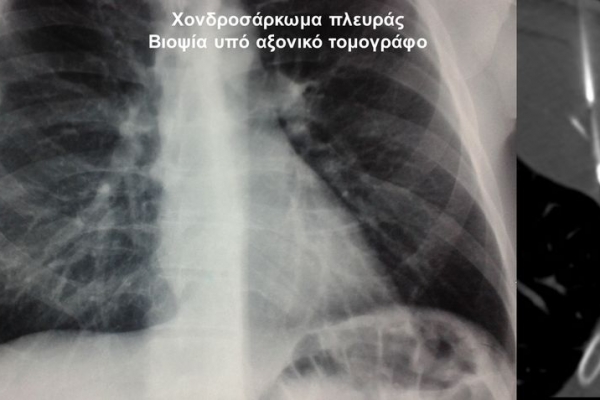

Η οστική βιοψία και η βιοψία όγκων μαλακών μορίων χρησιμοποιείται για την ιστολογική διάγνωση αλλοιώσεων (καλοήθων - κακοήθων / πρωτοπαθών ή μεταστατικών) ή για τη λήψη υλικού προς καλλιέργεια ώστε να αναδειχθεί το μικρόβιο που προκαλεί τη λοίμωξη του μυοσκελετικού συστηματος (πχ σπονδυλοδισκίτιδα). Η βιοψία υπό συνεχή απεικονιστική καθοδήγηση συμβάλλει στην υψηλή ακρίβεια τοποθέτησης της βελόνης εντός της βλάβης με ασφαλή προσπέλαση. Η χρήση σύγχρονων ομοαξονικών συστημάτων βιοψίας (coaxialtechnique) επιτρέπει την λήψη πολλαπλών δειγμάτων με μια μόνο παρακέντηση.